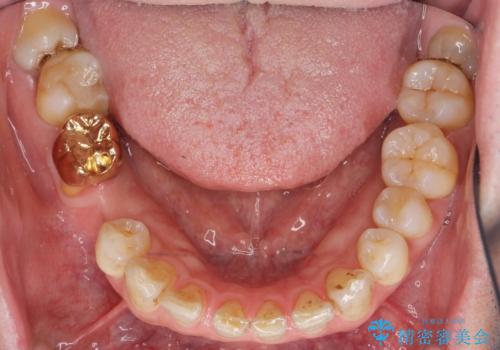

その後ブリッジの治療も希望され、オールセラミックのブリッジによる補綴を行いました。

ゴールド(PGA)クラウンの自然な咬み心地とブリッジの審美的な仕上がりに喜んで頂けました。

モチベーションが上がり、ホワイトニングもご希望され補綴前に行いました。

右下⑥5④ブリッジ:オールセラミッククラウン スタンダード